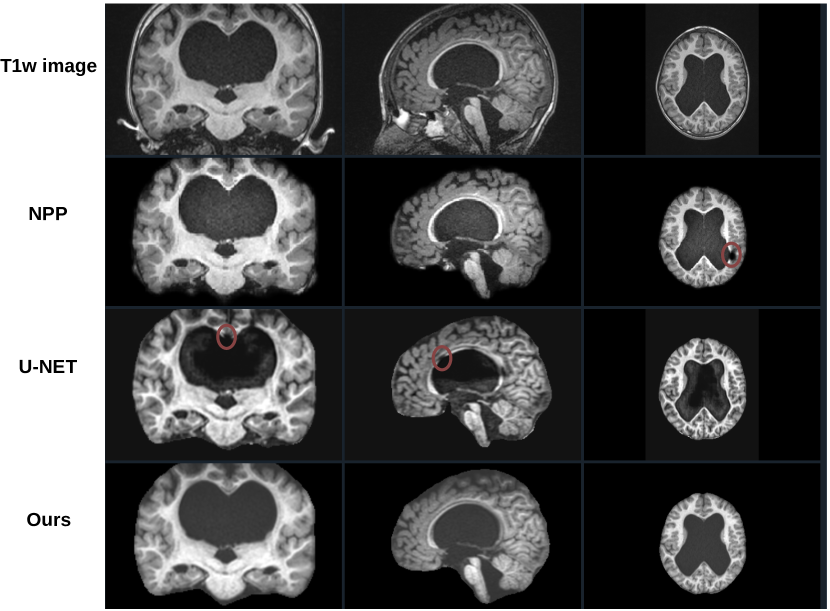

Across different datasets (Table 5, our method consistently achieved higher DICE (F1) scores, lower MSD values, and higher recall and accuracy rates compared to BET, NPP, and SynthStrip, highlighting its robustness and effectiveness in diverse segmentation tasks. Figure 3 illustrates a 3D MRI image along with the corresponding reconstruction and segmentation outcomes obtained using the proposed MGA-Net.

Refer to caption

Figure 3: From left to right: MRI image from an eight-year-old patient at HUPM, the reconstructed image using MGA-Net, and the brain boundary.

Figure 9 presents the three views of an eight-year-old preterm-born patient with reconstruction using NPP, U-Net, and the proposed method. As can be seen, the proposed method can successfully reconstruct the image even though there is an anomaly in the image, whereas NPP and U-Net have some problems in reconstructing the entire image (red circle in Figure 9.

The dataset obtained from Hospital Universitario Puerta del Mar (HUPM) originates from clinical settings, involving preterm neonates who may present with neurological abnormalities, such as abnormal tissue structures or atypical brain morphology (Figure 8). Some of these patients have been incorporated into the training dataset, while others are allocated to the test dataset to evaluate the model’s generalizability and robustness. Despite the inherent challenges associated with these variations, the results demonstrate that the performance of the proposed method on the test dataset is superior to that of conventional methods. This indicates that the proposed method can be effectively accommodated and adjusted for clinical abnormalities in its analyses. We attribute this robustness to the network architecture, which enhances its ability to generalize across uncommon and variant anatomical features.

Figure 9: Coronal, sagital and axial views (from left to right) of an eight-year-old preterm-born patient. The top image is the initial image.